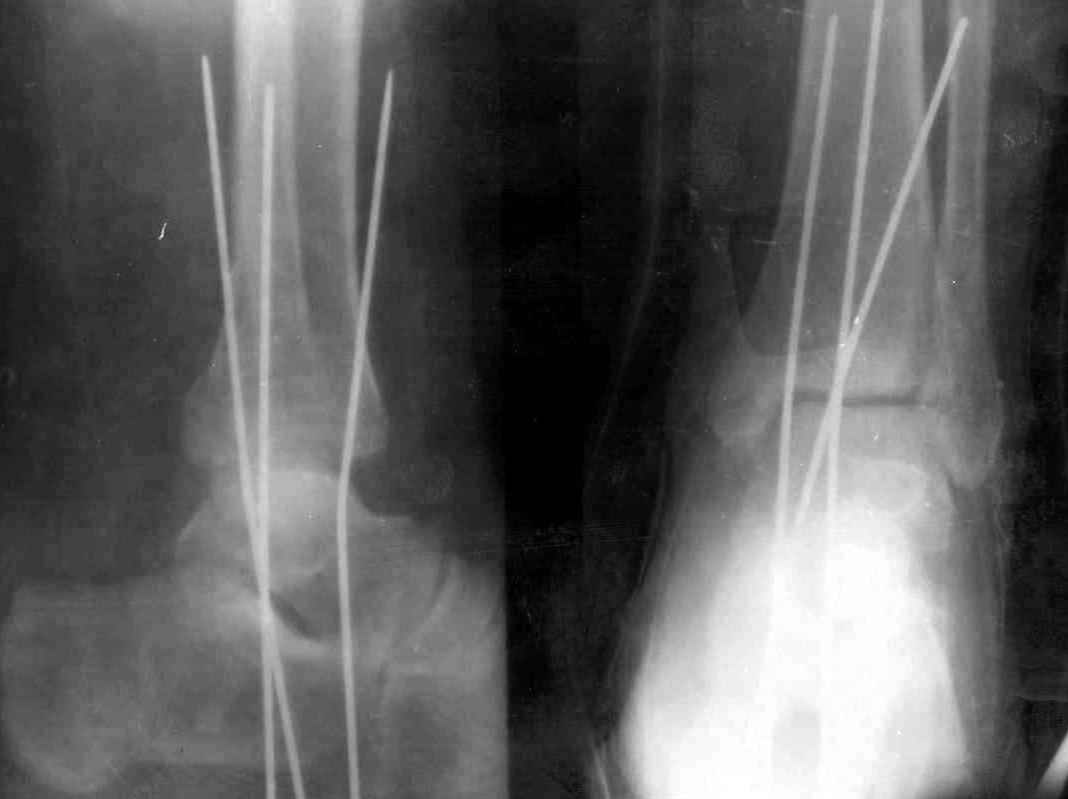

Ув. коллеги.

После проведенной дискуссии пришел к выводу, что трансартикулярная диафиксация не совсем приемлима с учетом современных методик остеосинтеза. Кроме того, вычитал, что хрящ разрушается на расстоянии до 0,5 см от места проведения спицы.

Пока я был в интернатуре, предпочитали осуществлять стабильный остеосинтез с ранней функцией. См. приложения и полнотекстный вариант

статьи.

Получился ожидаемый результат. Недостаточная длительность иммобилизации - подвывих, а жаль, первичная репозиция была замечательная, целесообразность назначения хондропротекторов, физиопроцедур вызывает сомнения.